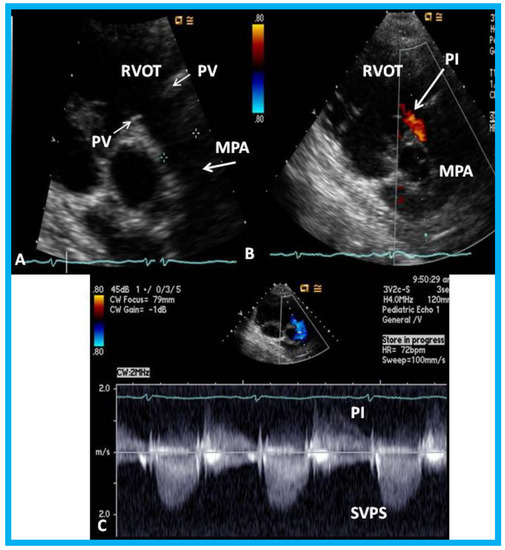

14. Unusual Complication of Supravalvular Pulmonary Artery Stenosis after a Nuss Procedure

An eleven-year-old female patient had a Nuss procedure for treatment of pectus excavatum [30]. A cardiac murmur was heard shortly before the planned Nuss bar removal at the age of thirteen years. Echocardiographic evaluation revealed external compression (Figure 21), causing supravalvar pulmonary stenosis [31]. Removal of the Nuss bar was performed which documented improvement on echo-Doppler studies (Figure 22). Usefulness of echo studies in evaluation of such issues was emphasized.

Figure 21. (A) Selected video frame from a parasternal short axis view showing echo dense structures (thick blue arrows) within and outside the main pulmonary artery (MPA): Pulmonary valve (PV) leaflets (small arrows) are shown and appear normal. The right ventricular outflow tract (RVOT) and proximal MPA are free of any echo-dense structures. (B) Color-Doppler mapping of the same structures as in panel A shows normal laminar (L) flow in the RVOT and proximal MPA and turbulent (T) flow starting in the proximal MPA, indicating obstruction. (C) Pulse Doppler sampling from the proximal MPA, which shows normal flow velocity. (D) Continuous wave Doppler sampling demonstrating high velocity flow across the MPA with a calculated peak instantaneous gradient of 93.7 mmHg and a mean gradient of 56 mmHg, indicating severe obstruction. Reproduced from Mazur L., et al. [31].

Figure 22. Echo-Doppler studies performed five months after removal of the Nuss bar: (A) Selected video frame from a parasternal short axis view demonstrating no echo dense structures in the right ventricular outflow tract (RVOT) and main pulmonary artery (MPA) that was seen prior to removal of the Nuss bar (Figure 20A). Pulmonary valve (PV) leaflets (arrows) are shown. (B) Color-Doppler mapping of the same structures as in panel A shows mild pulmonary insufficiency (PI) (arrow). (C) Continuous wave Doppler sampling demonstrating low Doppler flow velocity across the MPA with a calculated peak instantaneous gradient of 15 mmHg, indicating minimal supravalvular pulmonary stenosis (SVPS) and mild pulmonary insufficiency (PI). Reproduced from Mazur L., et al. [31].